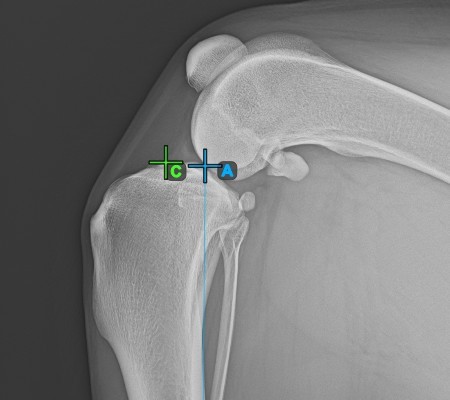

Start the measurement by marking the Eminentia Intercondylaris, which is located on the joint connecting the femur and the tibia.

The image below depicts the usual placement of the Eminentia Intercondylaris point.

Continue by marking the midpoint of the Cochlea, located at the end of the tibial bone. The line created between the Eminentia Intercondylaris and the midpoint of the Cochlea represents the long axis of the tibia.

The image below depicts the usual placement of the midpoint of the Cochlea.